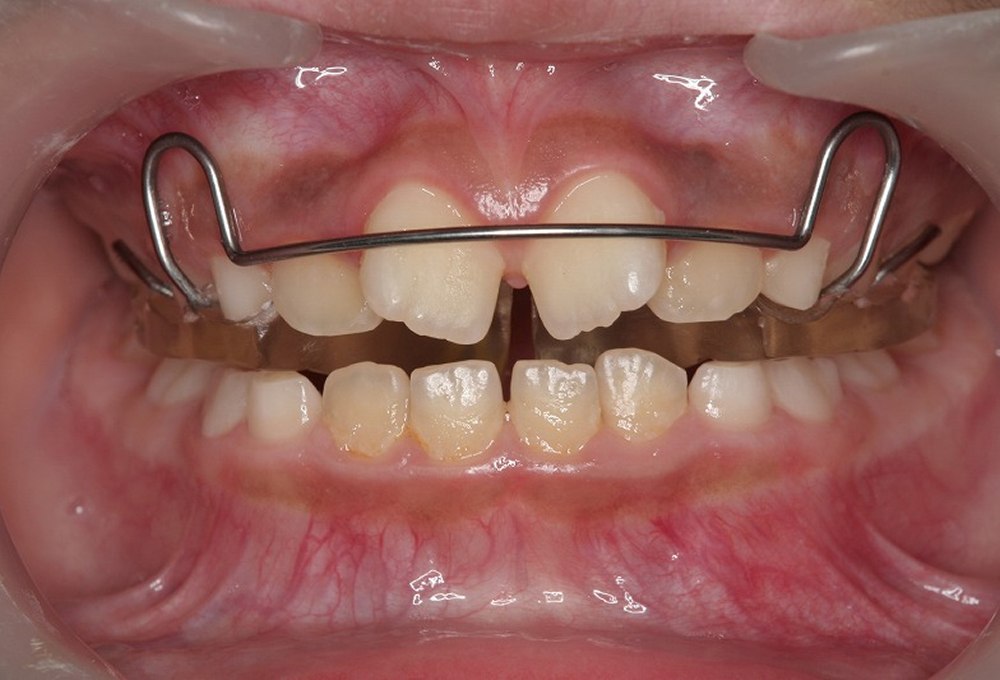

①術前 前歯部翼状捻転

③正面観